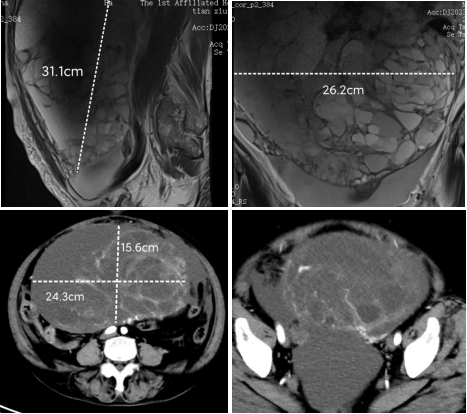

患者为老年女性,80岁,存在糖尿病、高血压等多种基础疾病,几个月前因腹部疼痛就诊,腹部膨隆尤为明显,检查提示腹盆腔巨大占位,大小约31cm×26cm×16cm,因肿瘤压迫,患者合并不全肠梗阻表现,饮食差、营养差,腹胀难忍,身心极为痛苦。穿刺活检提示:黏液性肿瘤,卵巢来源可能性大。辗转就诊于北京、广州等多家大型三甲医院,行介入栓塞治疗多次、化疗、中西医结合治疗等多种治疗,效果不甚理想。后多方打听来到妇科介入科就诊。

因患者高龄、肿瘤占据整个腹盆腔,且与肠管粘连严重,界限不清,手术难度极大,遂积极与郑州大学第一附属医院腹盆部肿瘤外科沟通,王刚成教授团队经过仔细阅片,充分术前评估及麻醉、心内等术前会诊后,为该患者实施“巨大体积卵巢癌根治术(腹盆腔巨大肿瘤切除+子宫双附件全切+大网膜切除+肠粘连松解(患者阑尾既往已切除)”,手术用时45分钟完整切除巨大肿瘤、子宫双附件及大网膜,游离并保护粘连肠管,术中顺利,出血较少。现已康复出院。